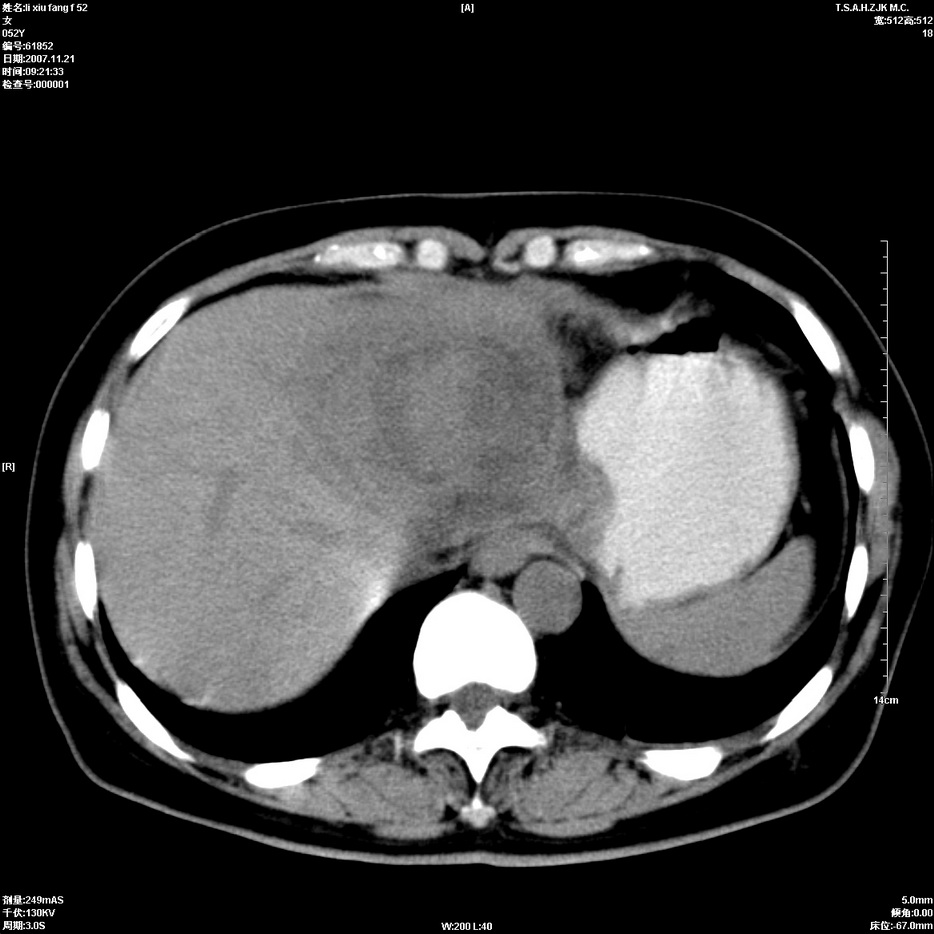

标题: CT12858:女,52岁,胎甲球蛋白861肝左叶占位,肝癌。下腔静 [打印本页]

标题: CT12858:女,52岁,胎甲球蛋白861肝左叶占位,肝癌。下腔静

肝左叶巨大低密度灶肿块,增强符合快进快出表现,有动静脉交通支;静脉期,下腔静脉内有充盈缺损,afp明显升高,支持肝癌并下腔静脉癌栓形成。

以下是引用拾荒者在2008-4-15 22:57:00的发言:[br]肝左叶巨大低密度灶肿块,增强符合快进快出表现,有动静脉交通支;静脉期,下腔静脉内有充盈缺损,afp明显升高,支持肝癌并下腔静脉癌栓形成。